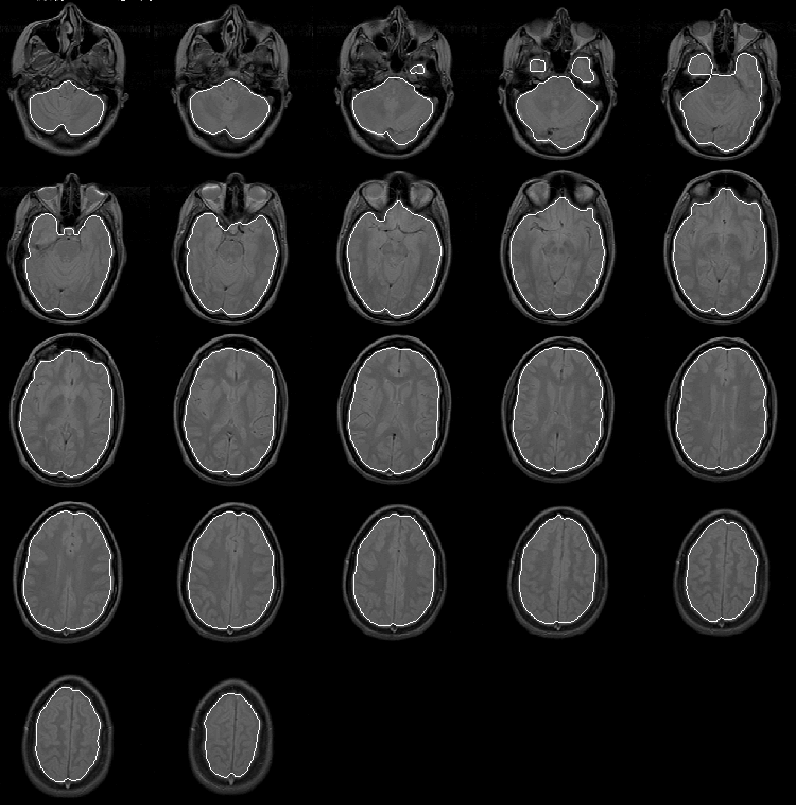

As shown in Figure 8.13, the Generate Initial Brain Mask produces an initial brain mask for Data Set 2 that is comparable to that produced for Data Set 1. The brain mask provides a good seed for the Generate Final Brain Mask process.

Figure 8.13: The initial brain mask for MRI Data Set 2 overlaid on the PD-weighted scan.

For Data Set 3 the Generate Initial Brain Mask process again produces a good initial brain mask to use as a seed for the Generate Final Brain Mask process. The mask is overlaid on the PD-weighted scan of Data Set 3 in Figure 8.14.

Figure 8.14: The initial brain mask for MRI Data Set 3 overlaid on the PD-weighted scan.

Figure 8.15 shows the initial brain mask for Data Set 4 overlaid on the PD-weighted scan. As with the previous three data sets, the mask is very good. In slices 11 through 14, the mask extends beyond the intracranial boundary due to the bright areas between the eyes and in the forehead region of the patient. Still, the mask is close enough to the intracranial boundary for the Generate Final Brain Mask process to work effectively.

Figure 8.15: The initial brain mask for MRI Data Set 4 overlaid on the PD-weighted scan.

The initial brain mask for Data Set 5 is overlaid on the PD-weighted scan in Figure 8.16. The mask is, again, very good. Only a small region of extremely low intensity brain voxels is missed in the lower left corner of slice 2.

Figure 8.16: The initial brain mask for MRI Data Set 5 overlaid on the PD-weighted scan.